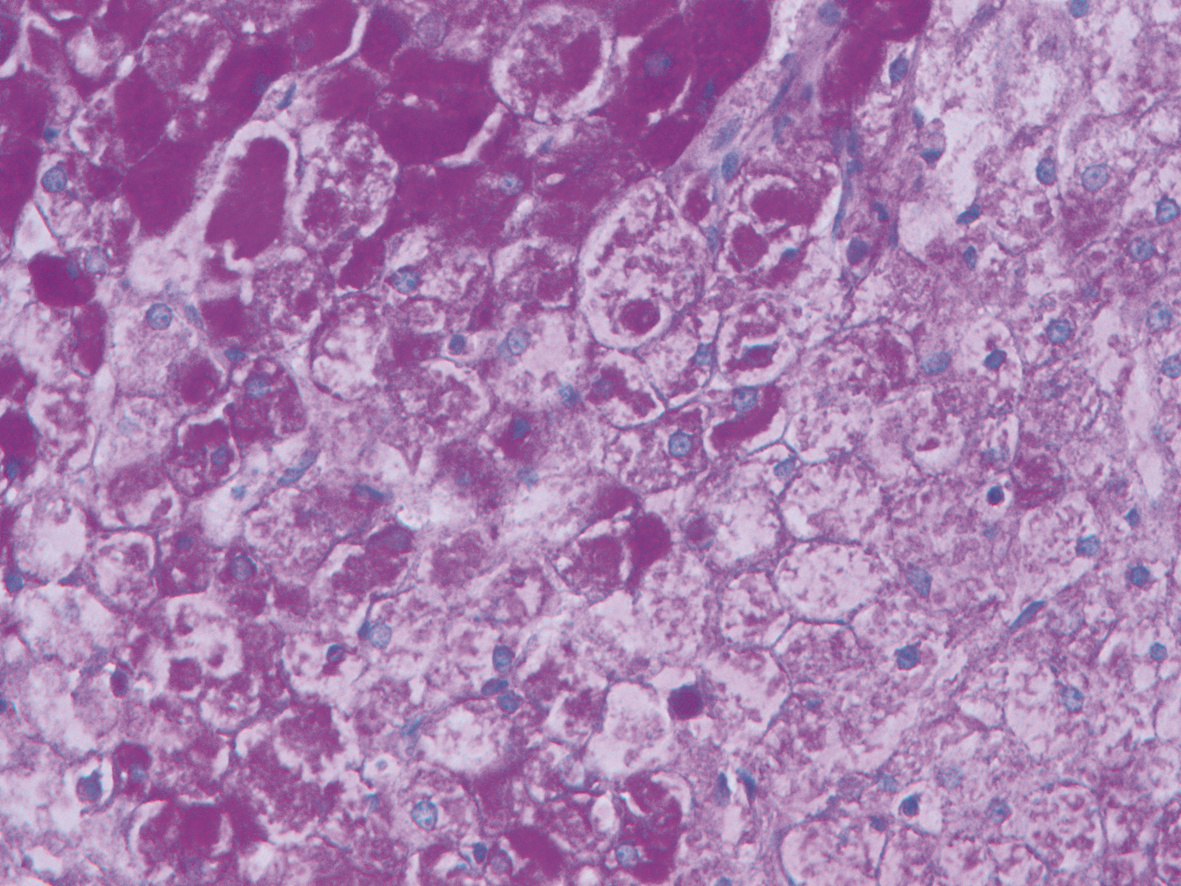

Schwannoma of the pancreatic tail: A case report

Jiachao ZHANG, Rong TANG, Zhensheng ZHANG, Pingping CHEN, Yongchao ZENG

2022, 38(8): 1878-1879. DOI: 10.3969/j.issn.1001-5256.2022.08.030

Abstract(685) HTML (278) PDF (3067KB)(72)

Abstract: